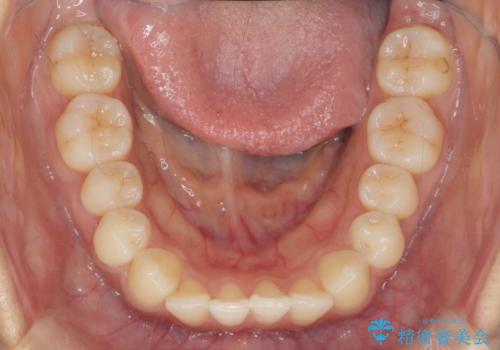

前歯のねじれ、すれ違いを改善 部分ワイヤー+マウスピース矯正

- 上下前歯のすれ違い、ねじれのある歯並びの矯正治療を求めて来院されました。

上顎前歯のみの部分ワイヤー治療を約6ヶ月行い、ねじれの問題を解決したのち、マウスピース矯正で細かな歯列を整えていきます。

前歯のすれ違いが改善することで噛みやすくなった。と矯正治療の結果に満足いただくことができました。